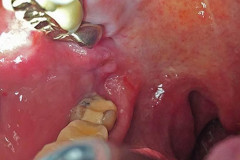

7 Դեկտեմբեր, 2016 11:05

65-ամյա կնոջ լնդի միջից դուրս բերածը շոկի մեջ գցեց բժիշկներին (լուսանկարներ 16+)